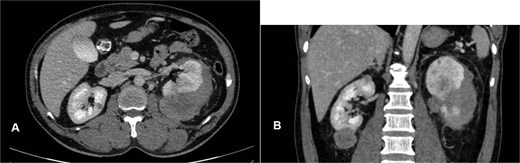

Abdominal magnetic resonance imaging (MRI) showed approximately seven to eight right renal masses (largest 32 × 35 × 37 mm) and five to six left renal masses (largest 62 × 55 × 55 mm). The renal lesions were iso- to mildly hypointense on T1-weighted imaging and mildly hypointense on T2-weighted imaging, without macroscopic fat. Post-gadolinium images demonstrated heterogeneous enhancement with central necrosis in the dominant masses (Fig. 3). Diffusion-weighted imaging showed marked restriction in the viable tumor components (Fig. 4). The dominant left renal mass, located in the mid kidney, demonstrated invasion of the posterior renal fascia. Subacute hemorrhage under the left renal capsule measured up to 24 mm in thickness.

Axial T1-weighted and T2-weighted MRI showing multiple solid renal masses with low signal intensity and a large left subcapsular hematoma.